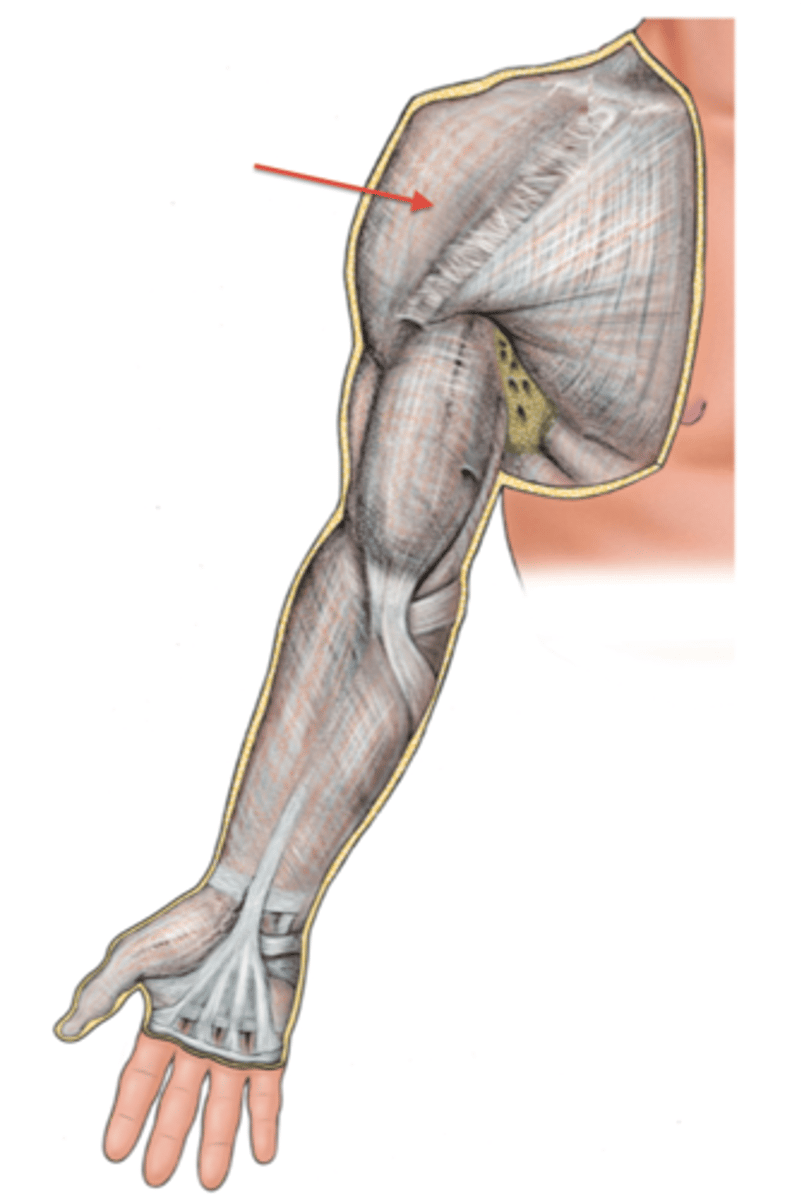

(Upper limb fascia) Fascia of arm region

Brachial fascia

(Fascia of arm region:) Brachial fascia

sheath of deep fascia that encloses the arm like a sleeve deep to skin and superficial fascia. It is continuous superiorly with the deltoid, pectoral, axillary, and infraspinous fascias, and inferiorly with the antebrachial fascia (at the level of the elbow)

- Contains Medial & Lateral intermuscular septa

(Brachial Fascia:) Medial & Lateral intermuscular septa

extensions of brachial fascia that attach to the bone, forming fascial compartments that limit spread of infection and hemorrhage in the arm

-Anterior (flexor) fascial compartment

-Posterior (extensor) fascial compartment

(Upper Limb Fascia:) Fascia of forearm region

Antebrachial fascia

(Fascia of forearm region:) Antebrachial fascia

sheath of deep fascia that encloses the forearm like a sleeve deep to skin and superficial fascia. It is continuous superiorly with the brachial fascia, and it thickens inferiorly to form bands over the distal portion of the radius and ulna

-Contains: Medial & Lateral intermuscular septa and Transverse bands